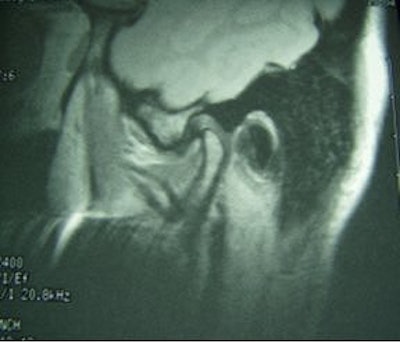

![]() |

Fifty-year-old woman with clicking and pain in both TMJs, 8-mm mandibular advancement, and MIO that decreased from 42 mm to 40 mm postoperative. Above, bilateral, right anterior disk displacement on MRI preoperative, which did not change on postoperative MRI, below. Images courtesy of Dr. Jessica Lee.